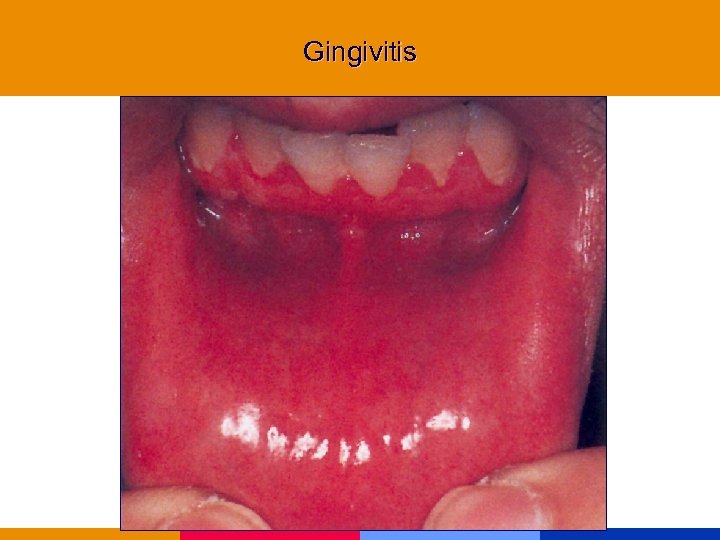

Gingivitis

Gingivitis

Gingivitis

Gingivitis